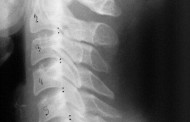

Прежде чем углубляться в методы лечения, давайте разберёмся, что такое артрит. Этот термин объединяет группу заболеваний, связанных с воспалением суставов. Самыми распространёнными формами являются остеоартрит и ревматоидный артрит. При остеоартрите происходит разрушение хрящевой ткани, а при ревматоидном – воспаление с аутоиммунной природой, когда иммунная система атакует собственные суставы.

Современная хирургия при артрите развивается в сторону минимального травмирования тканей. Артроскопия позволяет провести диагностику и лечение внутри сустава с помощью микроинструментов, что снижает восстановительный период и уменьшает риски осложнений.

При серьёзных повреждениях суставов выполняют эндопротезирование – замену больного сустава на искусственный. Сегодня эндопротезы изготавливаются из прочных и биосовместимых материалов, давая пациентам возможность вновь двигаться без боли и ограничений.